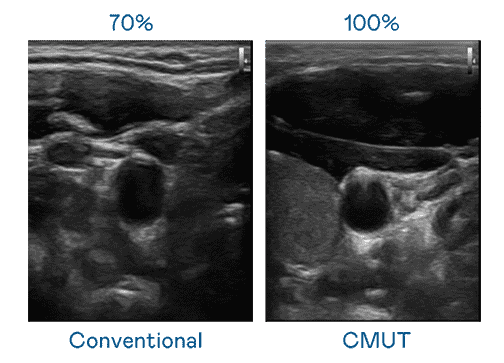

CMUT 技术是一种用电容式微机电元件来产生超音波讯号的技术。。。与传统 PZT 压电式技术相比,,,CMUT 频宽增加 30%,,,更宽频的超音波讯号让影像解析度大幅提升,,,,是实现高影像品质医疗超音波扫描、、促进精准医疗发展的关键技术。。

大频宽带来超清晰影像

超音波影像的解析度高低,,,首先取决于探头能发出的讯号频宽。。。。EBpay CMUT 可提供高清晰的超音波讯号,,提供高频宽、、、高灵敏度、、影像纹理细节更高的超音波影像,,,协助医护人员缩短影像判读时间及利用精准的医疗影像进行诊断。。。